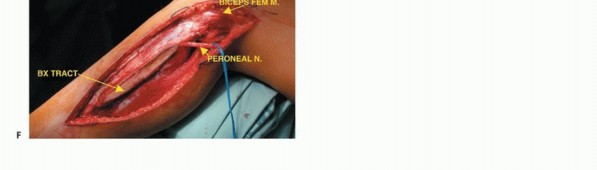

تشريح الشظية القريبة

تُعد الشظية القريبة (الرأس والجزء العلوي من العظم) موقعًا رئيسيًا لالتصاق الرباط الجانبي الوحشي (LCL) ووتر العضلة ذات الرأسين الفخذية. هذه الروابط ضرورية لاستقرار مفصل الركبة الجانبي. الأهم من ذلك، أن العصب الشظوي المشترك يلتف حول قاعدة رأس الشظية ليدخل نفق العضلة الشظوية الطويلة، مما يجعله عرضة للإصابة أثناء جراحة الأورام في هذه المنطقة.

الاستئصال من النوع الثاني (Type II Resection):

- الإشارة: يُستخدم لعلاج الأورام الغرنية عالية الدرجة، والتي عادةً ما يكون لديها تدمير قشري كبير مع امتداد خارج العظم.

- الإجراء: يشمل إزالة الشظية القريبة والمفصل الظنبوبي الشظوي، والحجرات العضلية الأمامية والجانبية، والعصب الشظوي، والشريان الظنبوبي الأمامي بشكل كامل. يتطلب هذا النوع ربط الشريان الظنبوبي الأمامي وقد يتطلب أيضًا التضحية بالشريان الشظوي.

- الحفاظ: لا يتم الحفاظ على العصب الشظوي والشريان الظنبوبي الأمامي.

الشق الجراحي (القطع الجراحي)

يُستخدم "الشق الشظوي النفعي" (utilitarian fibular incision)، والذي يسمح بكشف واستئصال الأورام في جميع مستويات الشظية. يمتد هذا الشق من العضلة ذات الرأسين فوق مفصل الركبة، فوق الجزء الأوسط من الشظية، إلى الأمام باتجاه قمة الظنبوب، ثم ينحني خلفيًا وبعيدًا إلى الكاحل. يسمح هذا بتطوير سدائل جلدية عضلية أمامية وخلفية كبيرة.